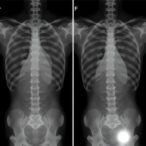

At the heart of the study was the hypothesis that resistance training performed in water can mitigate age-related brain atrophy by stimulating neuroplastic mechanisms and modulating systemic biochemical markers responsible for neural preservation. To test this, the researchers enrolled an elderly population, randomized into intervention and control groups. Subjects engaging in the aquatic resistance regimen demonstrated significant enhancements in key brain regions associated with memory, executive function, and motor control, as assessed through advanced neuroimaging techniques such as volumetric MRI and diffusion tensor imaging.

The structural benefits unearthed were complemented by measurable biochemical changes. Participants showed elevated concentrations of brain-derived neurotrophic factor (BDNF), a critical protein that supports neuron survival, differentiation, and synaptic plasticity. Intriguingly, inflammatory biomarkers, often elevated in aging and linked to neurodegeneration, were notably reduced in the aquatic training group, suggesting a systemic anti-inflammatory effect induced by this specific exercise modality.